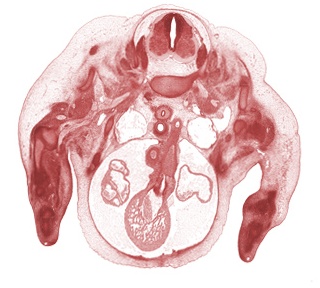

IntroductionStage 18 embryos have a greatest length of 13 to 17 mm and an estimated postfertilization age of approximately 44 days. In the head region the tip of the nose becomes discernable as well as the volmeronasal organ, eyelids, and nasolacrimal ducts. The auricular hillocks begin to blend to form parts of the definitive external ear. Two or three semicircular ducts form from the otic vesicle in the otic capsule. The subarachnoid space surrounds the entire central nervous system and the choroid plexus is forming in the roof of the 4th ventricle. Read more...New structures include brachiocephalic artery, clavicle, femoral nerve, intervertebral discs, pyloric antrum of stomach, scapula, suprarenal gland cortex. |

Section 437(View All Sections) |